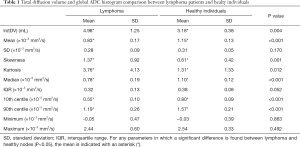

Test results—global ADC

The mean values and SD of tDV and gADC parameters calculated for each patient are shown in Table 1. We found that the mean, median, 10th and 90th centiles gADC values were significantly lower in malignant than in normal lymph nodes. By contrast, ln(tDV), gADC skewness and kurtosis were significantly larger in lymphoma. The gADC SD, IQR, minimum and maximum gADC showed no significant difference between malignant and normal lymph nodes (each P>0.052).

Table 2 shows the performance of the significant gADC discriminators. The order of the diagnostic accuracies of gADC parameters by AUC performance from highest to lowest was: 10th centile, mean, median, 90th centile, skewness and kurtosis. Figure 2 visualises the overlap of gADC parameters between lymphoma and healthy individuals. There was no significant difference of AUC between mean and median gADC, 10th and 90th centile gADC (each P>0.131). Mean gADC AUC was significantly larger than gADC skewness AUC (P=0.032) and gADC kurtosis (P=0.004). 10th centile and median gADC AUC were significantly larger than for gADC kurtosis (each P<0.010). Median and 90th centile gADC AUC were significantly larger than for gADC skewness (each P<0.043). In correspondence to the AUC, the highest Youden index among gADC histogram parameters was calculated for the 10th centile gADC at a threshold of 0.67×10−3 mm2/s, smaller values identifying disease with 91% sensitivity and 95% specificity. A median gADC value less than 0.91×10−3 mm2/s identified disease with 87% sensitivity and 95% specificity. 81% sensitivity and 95% specificity was shown for a threshold mean ADC value of 0.95×10−3 mm2/s. Sensitivity of the 10th centile cut-off was significantly larger than for the mean gADC cut-off (P=0.046). Exemplar maximum intensity projections delineating lymph nodes of a lymphoma patient and a healthy volunteer are demonstrated in Figure 3. Figure 4 visualises the corresponding gADC histograms of lymphoma and healthy nodes of this particular patient (A) as well as the ADC distribution across all study subjects in both groups (B). No gADC parameter showed significant difference between different lymphoma subtypes (each P>0.324).